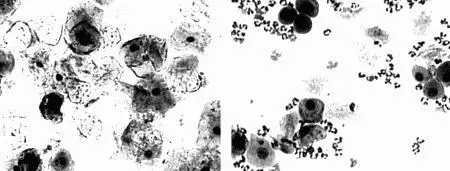

Фиг 22 Вагинальные выделения кошки а Выделения типичные для фазы - фото 6

Фиг. 2.2.

Вагинальные выделения кошки (а). Выделения, типичные для фазы эструса. Большая часть клеток представляет собой безъядерные кератинизированные клетки или клетки с пикнотическим ядром. Присутствуют промежуточные клетки (b). Выделения, характерные для метэструса, — «течки», иногда наблюдаемой у кошек в конце эструса. Присутствуют поверхностные и промежуточные клетки, повышено содержание лейкоцитов. Этот короткий метэструс наблюдается в течение 24–48 часов (см. Приложение)